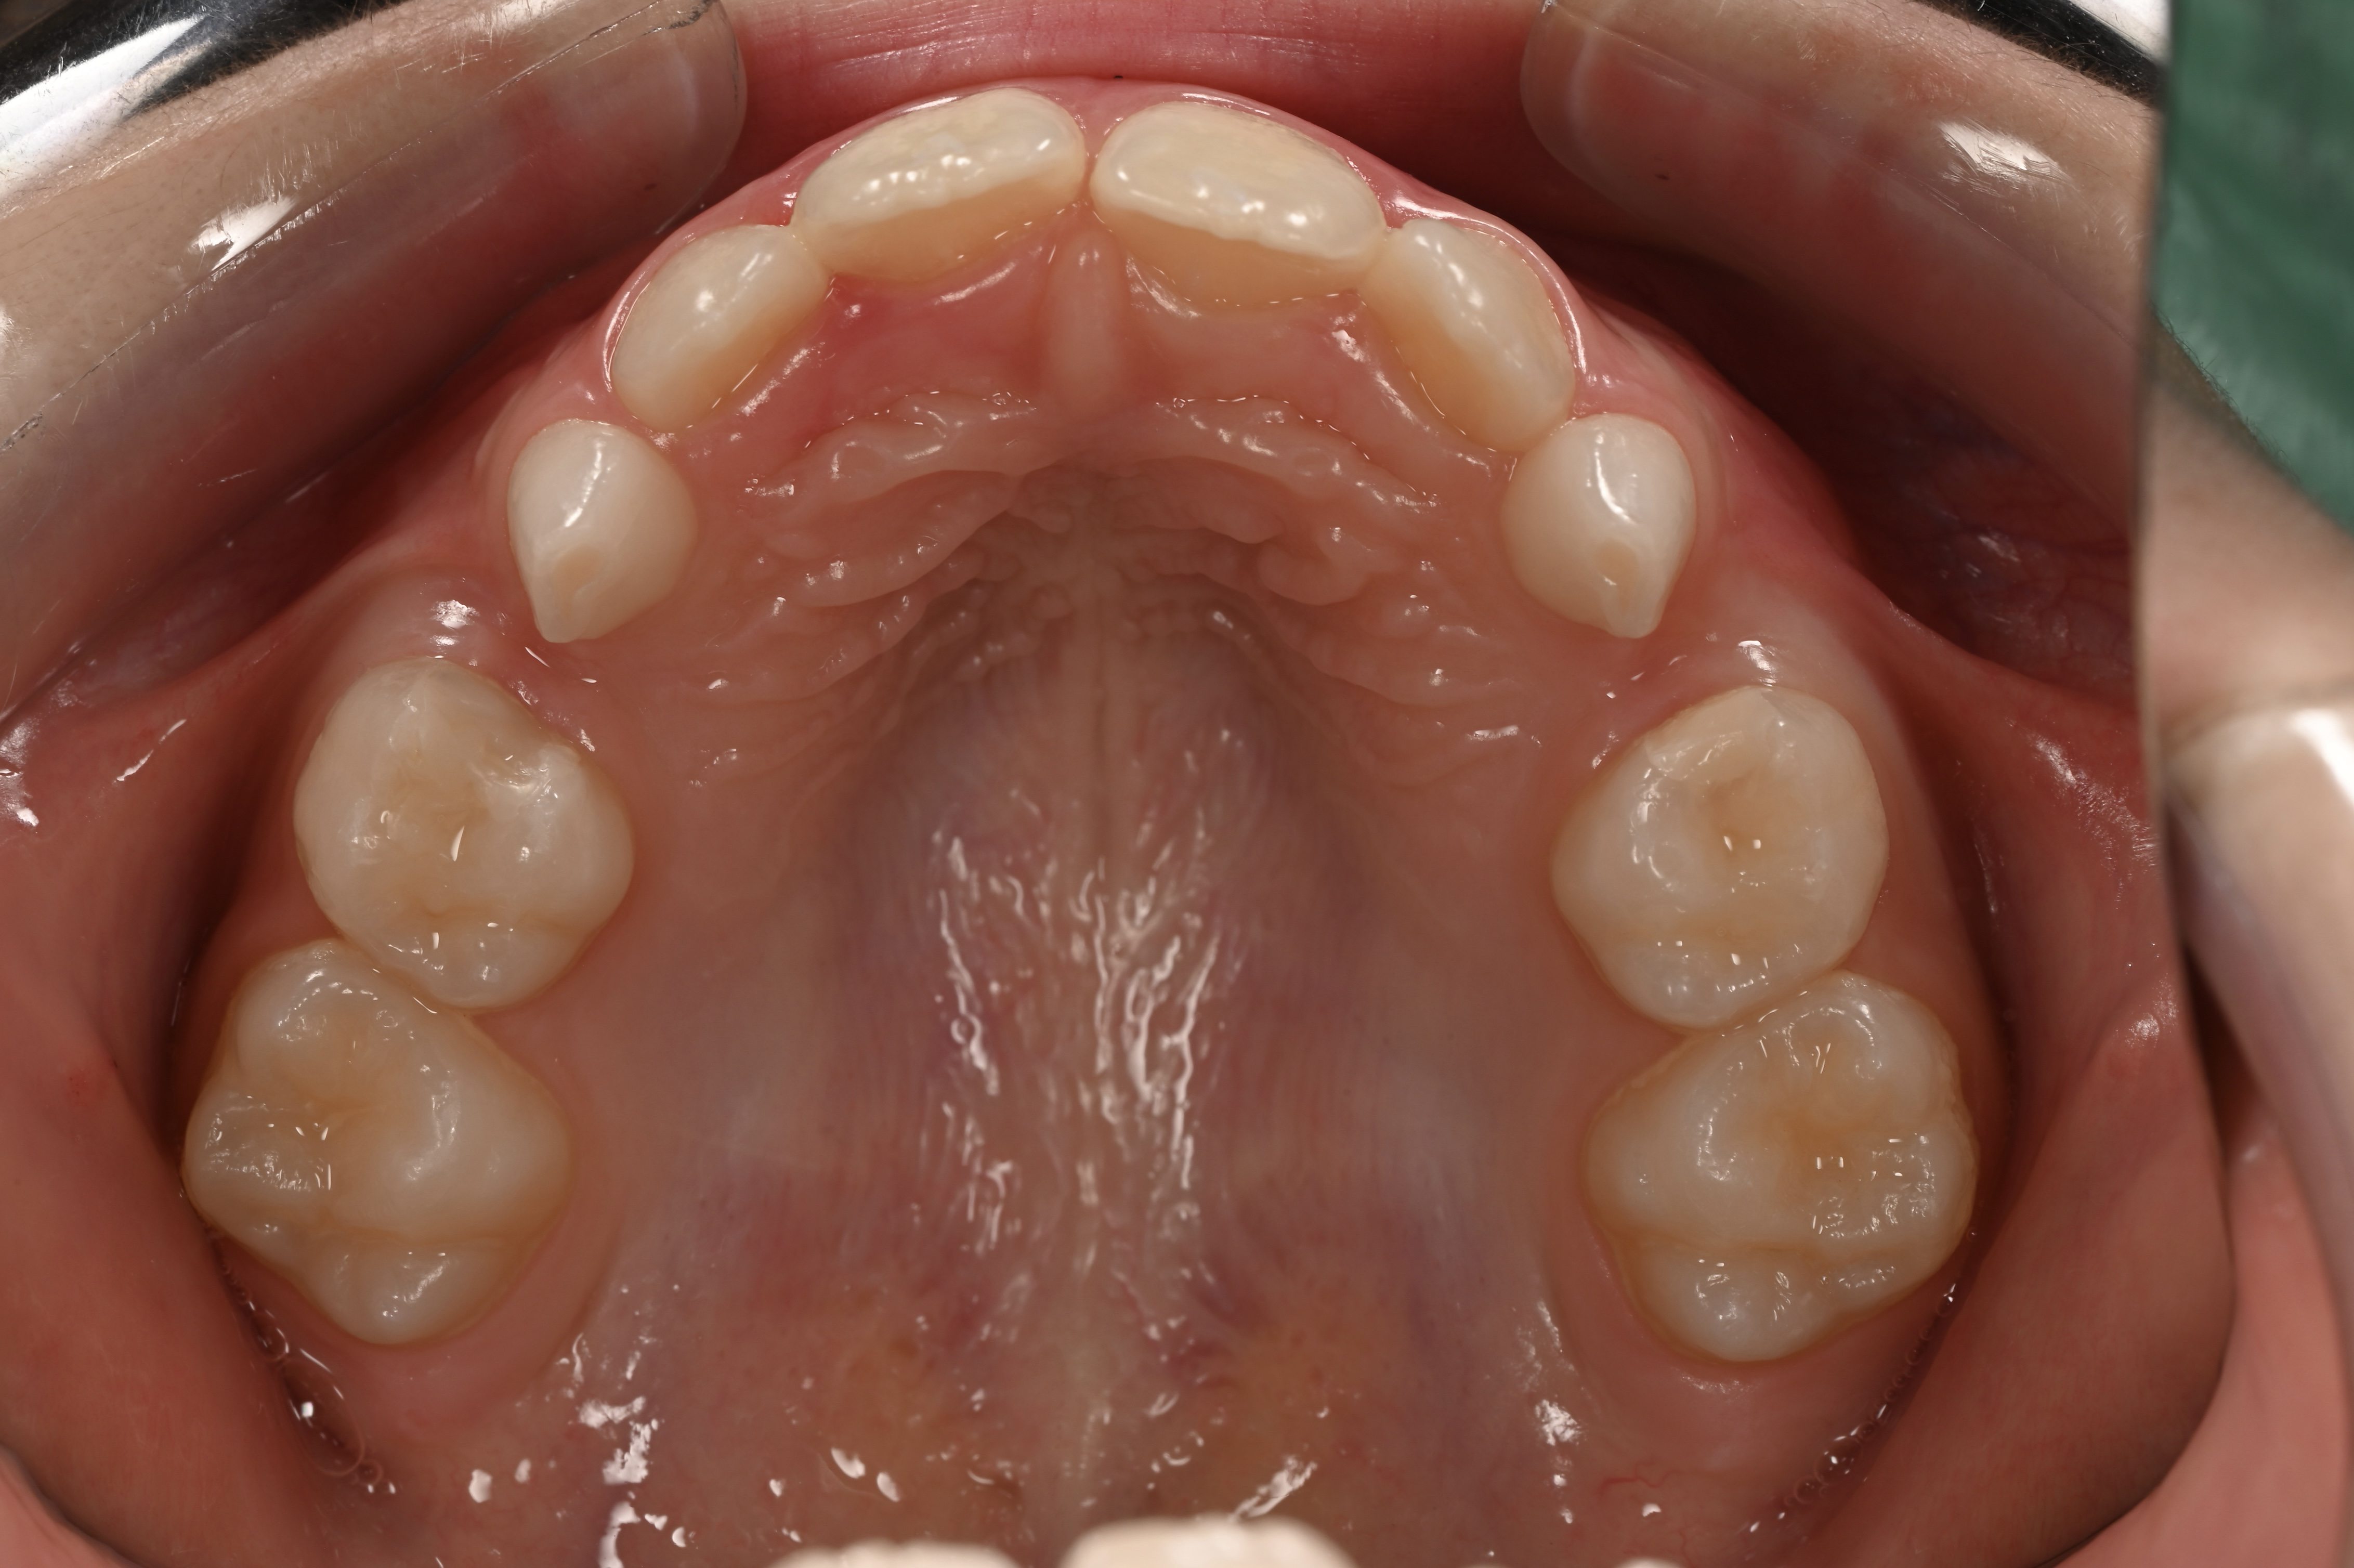

- Апарат для утримання місця — після передчасного видалення молочного зуба, щоб уникнути скупчення постійних зубів у майбутньому та, як наслідок, неправильного прикусу.